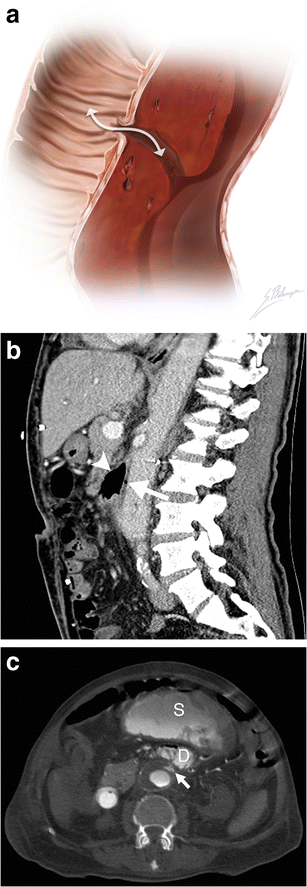

Aortoenteric fistula

Aortoenteric fistula. a Illustration depicts a fistulous tract connecting a bowel loop to an aortic aneurysm. The white double-headed arrow shows communication between the structures allowing bowel gas to infiltrate into the aortic wall and blood to leak into the bowel lumen. b Sagittal enhanced CT image of a 73-year-old man demonstrates an aortoenteric fistula. Intraluminal gas (white arrow) is observed within the AAA, and normal fat planes between the aneurysm and the third portion of the duodenum are lost (white arrowhead). c Axial enhanced CT of an 82-year-old man who presented with massive lower gastrointestinal bleeding and a history of previously repaired AAA. Active contrast extravasation (white arrow) into the third portion of the duodenum (D) and the stomach (S) can be seen in this patient with an aortoenteric fistula